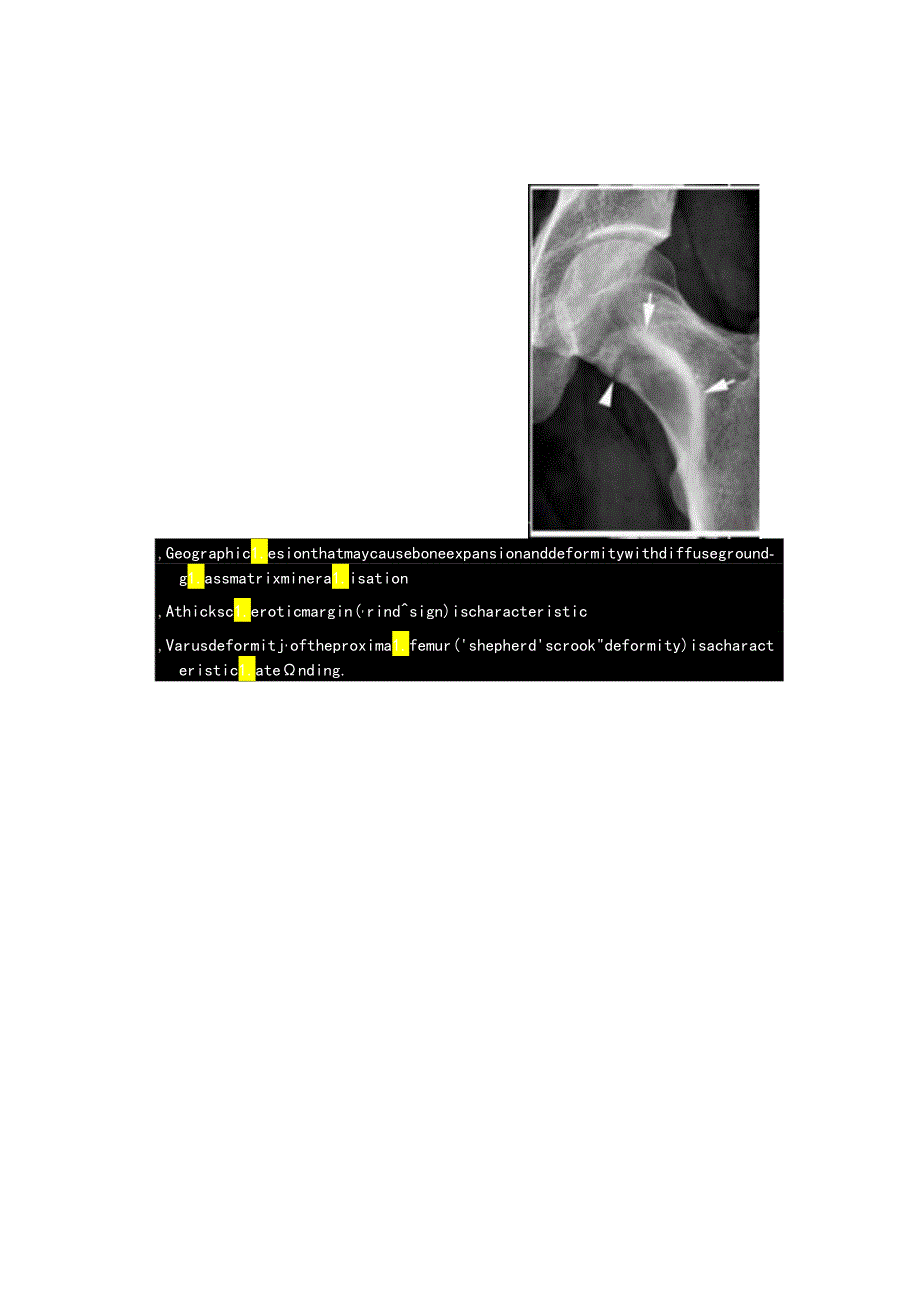

1、临床纤维异常增殖症病理及影像学表现X线检查示纤维异常增殖症(Fibrousdysp1.asia.FD)病变位于确腔内,多见于骨干,病变区域多透亮,很少情况卜出现高密度影(基质钙沉积时可出现),正常的骨小梁结构消失,代之以细颗粒”毛玻璃”样,有时病变周围的硬化骨带则可组成“果皮征”(rindsign)。图示:FD是一类良性纤维一骨肿瘤:化生的纤维组织构成的不成熟骨组织替代了正常的板状骨结构,约占良性骨肿瘤的5虹10%,由于许多患者无症状、未确诊,纤维异常增殖症的真实发病率很难估计。约75%的患者在30岁前发病,发病率无性别及种族差异。任何骨骼均有可能受累,但纤维异常增殖症多侵犯股骨(尤其是股骨颈

2、)、胫骨、骨盆、肋骨、颅骨、头面骨及椎体。约70M80%的患者为单处骨骼发病,而20V30%患者为多处部位发病,其中两种较著名的多发纤维异常增殖症业已被报道(McCune-A1.bright综合征和Mazabraud综合征)。,Geographic1.esionthatmaycauseboneexpansionanddeformitywithdiffusegroundg1.assmatrixminera1.isation,Athicksc1.eroticmargin(,rindsign)ischaracteristic,Varusdeformitj,oftheproxima1.femur(shepherdscrookdeformity)isacharacteristic1.atending.Radiographica1.features1.ongandshorttubu1.arbones- radio1.ucent1.esionindiaphysisormetaphysiswithSc1.eroticborder-RINDSIG- withendostea1.sca1.1.oping- Withorwithoutboneexpansion- Absenceofperiostea1.reaction